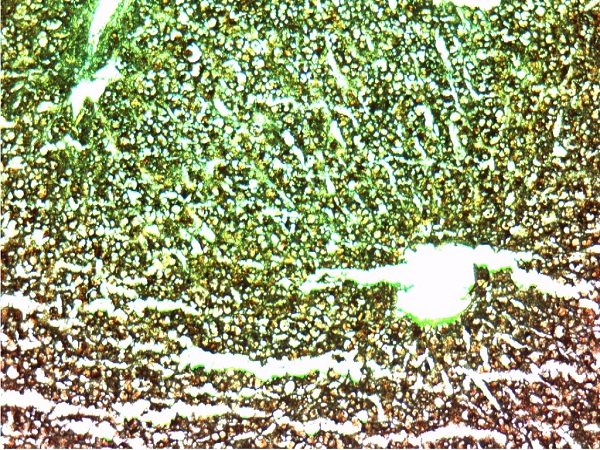

肝淀粉样变1(淀粉染色)10X10